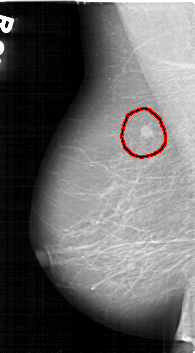

D_4125_1.LEFT_MLO

FILE: D_4125_1.LEFT_MLO.OVERLAY

TOTAL_ABNORMALITIES 1

ABNORMALITY 1

LESION_TYPE MASS SHAPE IRREGULAR MARGINS SPICULATED

ASSESSMENT 3

SUBTLETY 4

PATHOLOGY MALIGNANT

TOTAL_OUTLINES 1

BOUNDARY